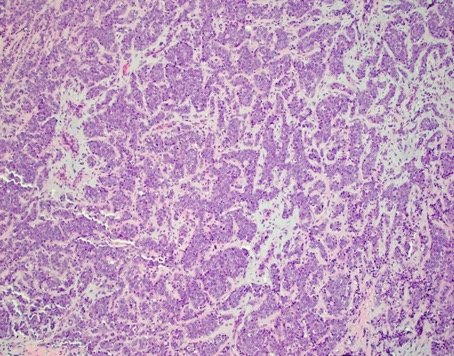

Case history: 17-year-old female with large, solid adnexal mass.

What is the diagnosis?

- Germ cell ...